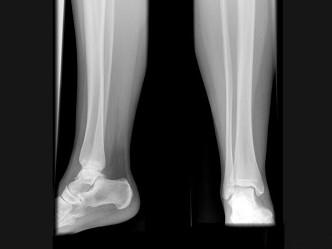

女,请根据其正常小腿影像图像,判断其最可能的年龄 ( )A、12岁左右B、8岁左右C、20岁左右D、16岁左右E、4岁左右

问题 女,请根据其正常小腿影像图像,判断其最可能的年龄 ( )

选项 A、12岁左右 B、8岁左右 C、20岁左右 D、16岁左右 E、4岁左右

答案 B